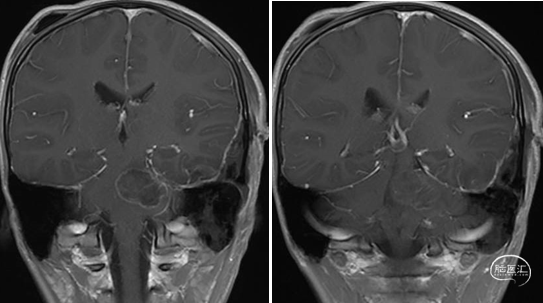

术前MRI

术后MRI